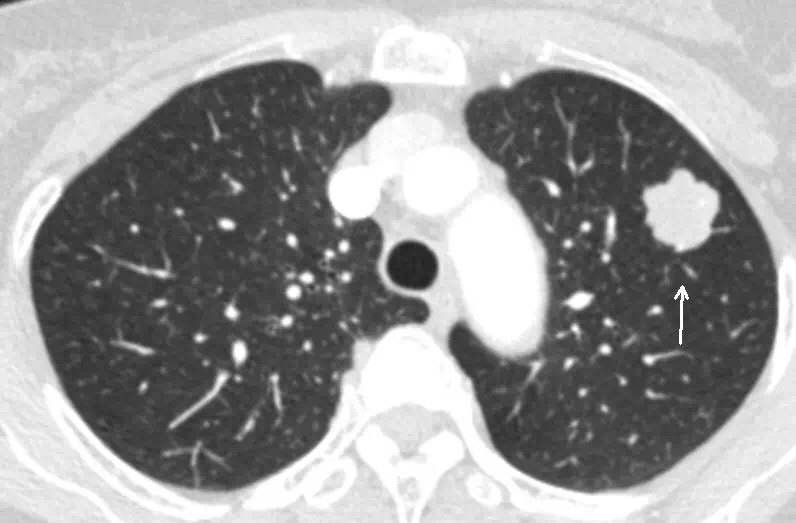

直径在10-30mm的肺结节,如果能通过药物治疗有明显效果,或者是典型的良性结节,这种可以不用手术切除,其余的一概支持切除。

比较麻烦的是比较小的磨玻璃结节。手术切除似乎有过度治疗的嫌疑,不切除也不放心,担心它长大或者癌变。

单纯的磨玻璃小结节,直径小于5mm,暂时不用切,注意复查,半年复查1次。

直径在5-10mm的磨玻璃结节,暂时不用手术,3个月复查1次。

结节可以通过药物进行治疗,如果是炎性结节一般可以缩小甚至消失的。如果出现结节长大,或从磨玻璃样的结节逐渐长成实性结节,不用犹豫了,切除吧。毕竟如果癌变了就麻烦了。